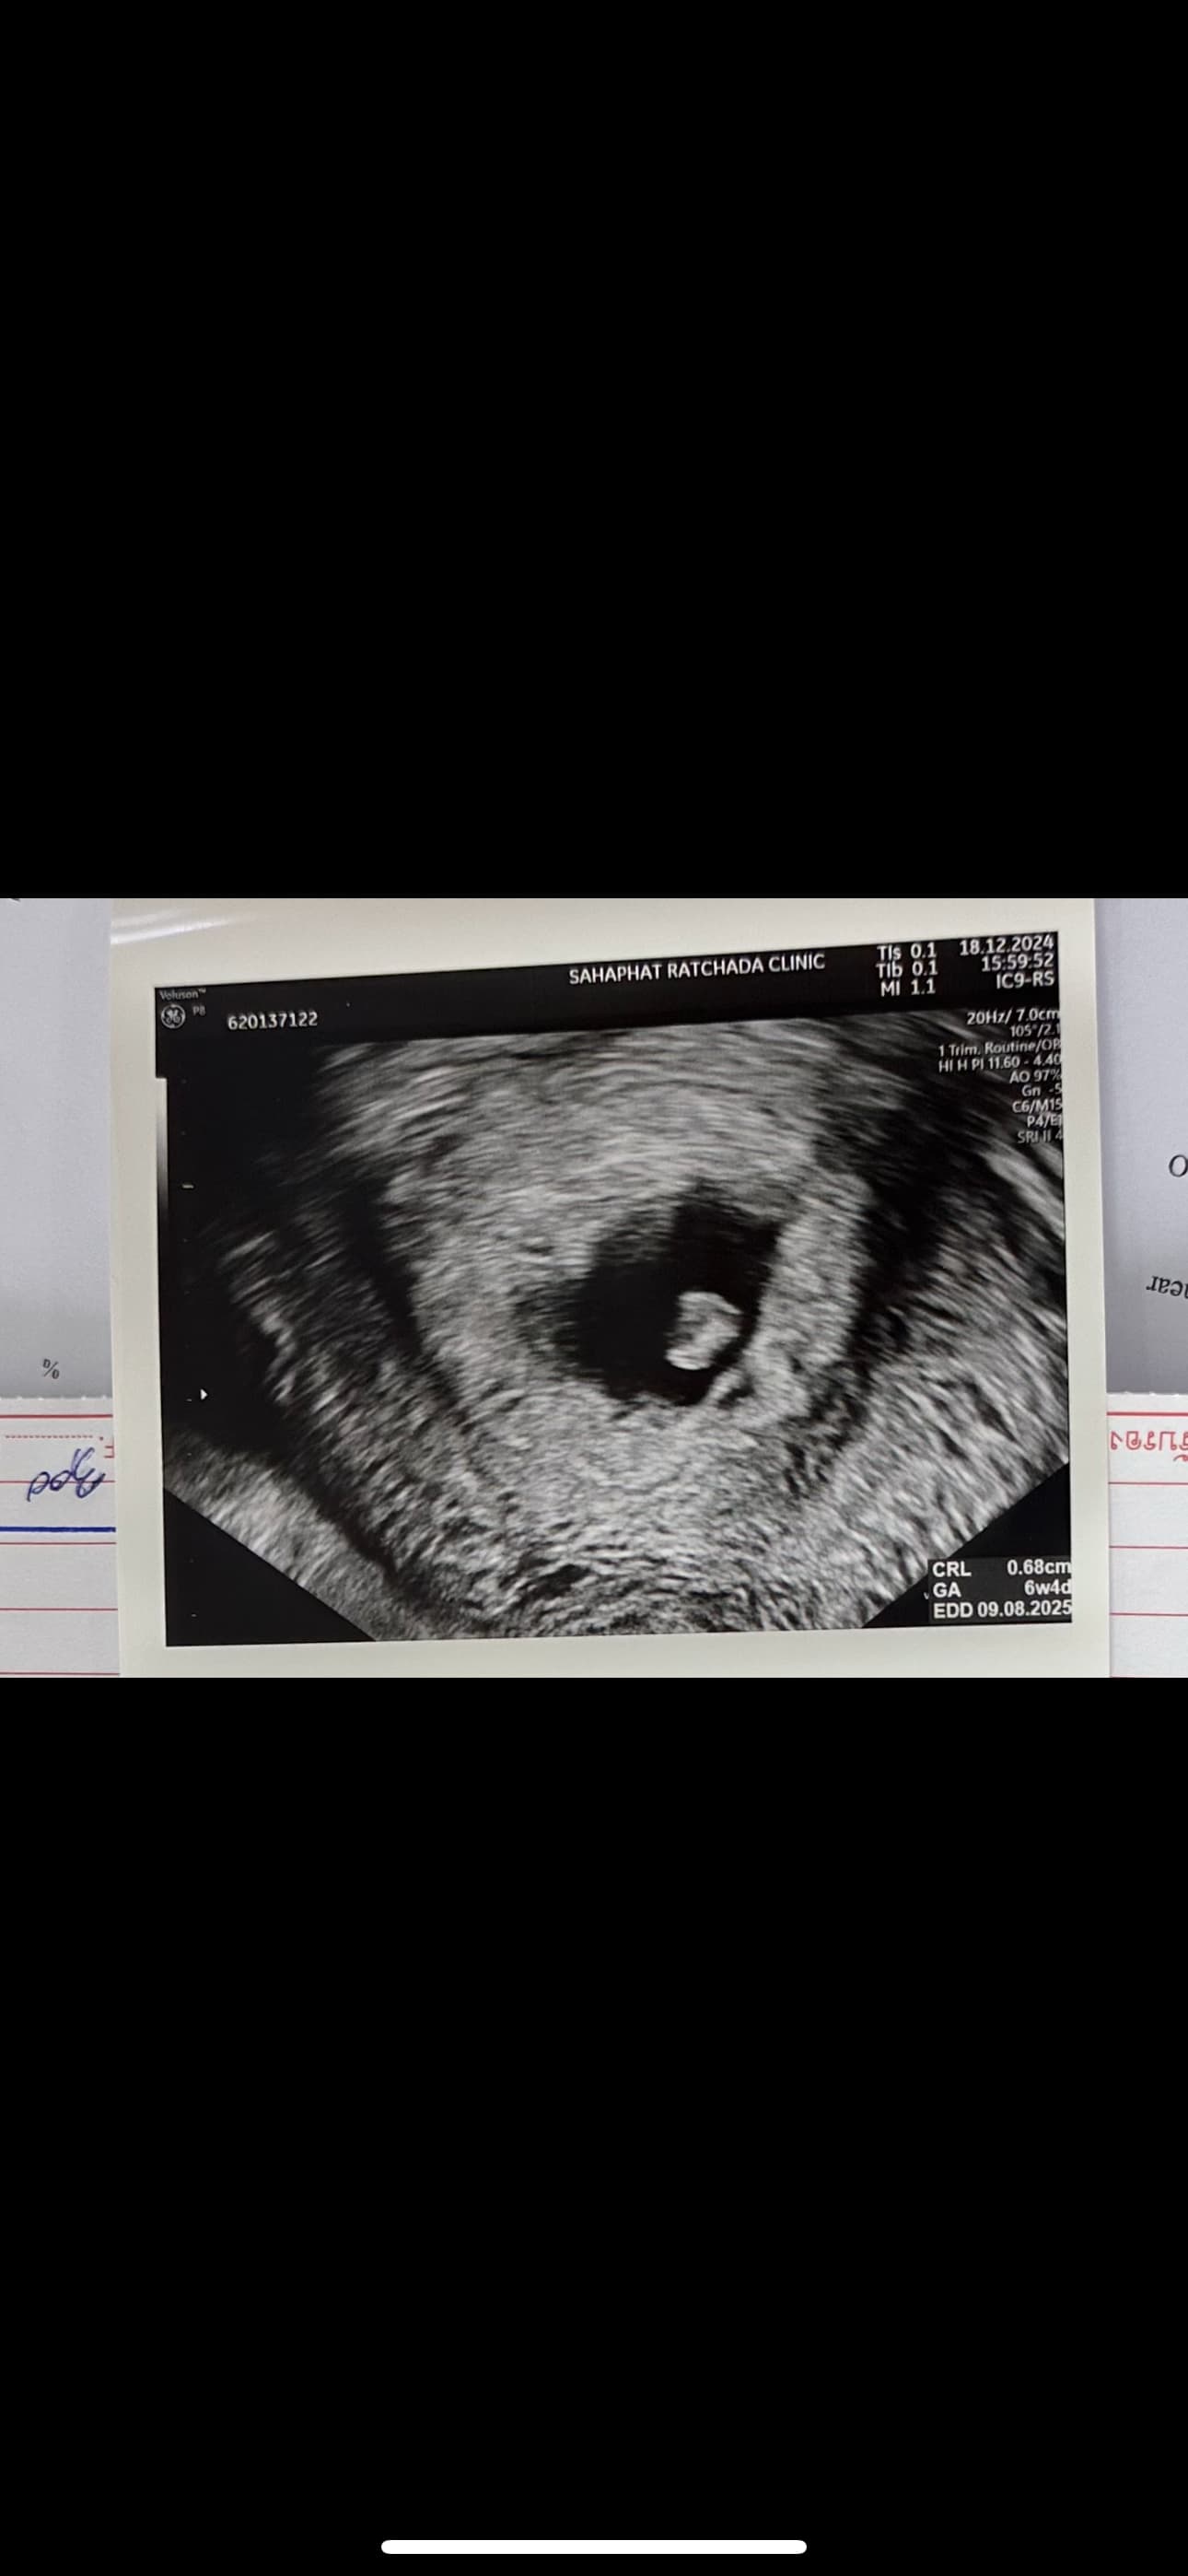

- หากรอบเดือนของคุณไม่ปกติหรือไม่สามารถระบุ LMP ได้อย่างชัดเจน อาจใช้ข้อมูลจากอัลตร้าซาวด์เพื่อช่วยประเมินอายุครรภ์โดยการวัดเส้นผ่านศูนย์กลางของถุงตั้งครรภ์ (Gestational Sac Diameter) หรือความยาวของตัวอ่อน (CRL: Crown-Rump Length) เพื่อถอยกลับไปประมาณวันที่อาจมีการปฏิสนธิค่ะ

- อัลตร้าซาวด์ในช่วงต้นของการตั้งครรภ์ (อายุครรภ์ต่ำกว่า 8 สัปดาห์) มักให้ข้อมูลที่แม่นยำที่สุดเมื่อใช้คำนวณอายุครรภ์และวันที่คาดว่าจะปฏิสนธิค่ะ

จากผลอัลตร้าซาวด์ที่คุณได้แสดงให้ดูในภาพ การระบุวันที่ของประจำเดือนล่าสุดอาจไม่สามารถทำได้โดยตรงจากภาพถ่ายค่ะ เพราะผลการอัลตร้าซาวด์เน้นที่การตรวจวัดขนาดของถุงตั้งครรภ์และตัวอ่อนเพื่อคำนวณอายุครรภ์ อย่างไรก็ตาม ผลอัลตร้าซาวด์สามารถช่วยให้เราประเมินได้ว่าอายุครรภ์ประมาณเท่าไหร่ ณ วันที่ทำการตรวจ โดยใช้ข้อมูลดังต่อไปนี้:

การวัดขนาดถุงตั้งครรภ์ (Gestational Sac Diameter) และตัวอ่อน (CRL):

- ขนาดของถุงการตั้งครรภ์และตัวอ่อนในระยะต้นๆ ของการตั้งครรภ์ (ช่วงอายุครรภ์ต่ำกว่า 8 สัปดาห์) สามารถบ่งบอกถึงอายุครรภ์ได้อย่างแม่นยำที่สุดค่ะ

- เมื่อทราบอายุครรภ์ เราสามารถถอยเวลาย้อนกลับเพื่อประมาณวันที่ที่อาจมีการปฏิสนธิได้ค่ะ โดยปฏิสนธิมักเกิดขึ้นในช่วงประมาณกลางของรอบเดือน หรือใกล้ช่วงไข่ตกค่ะ

การประเมินวันที่ปฏิสนธิ:

- หากคุณไม่สามารถระบุวันที่เริ่มต้นของประจำเดือนล่าสุดได้ แพทย์อาจใช้ผลจากการอัลตร้าซาวด์เป็นตัวช่วยในการระบุวันเริ่มต้นของการตั้งครรภ์ค่ะ โดยคำนวณถอยกลับไปจากอายุครรภ์